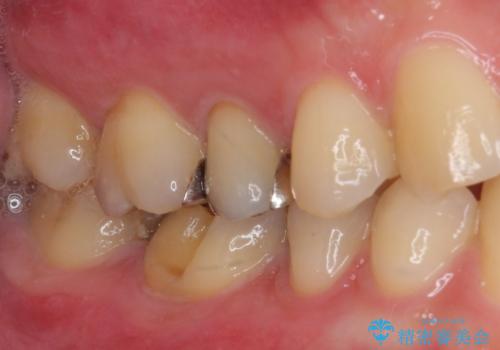

- 奥歯が欠けてしまったとのことで来院された患者様です。

おそらく歯が欠けて、装着されていた銀歯が外れてしまったと思われましたが、患者様はあまりはっきりとは覚えていないとのことでした。

咬合力が強いため、強化セラミッククラウンでの補綴治療を行うこととしました。